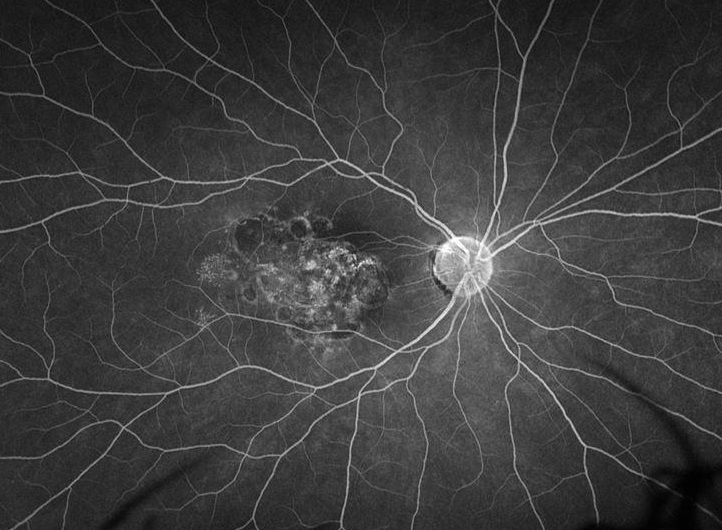

An inactive, chronic toxoplasma macular scar in the right eye of a healthy 23-year-old female patient. She reported to have had poor vision in this eye since very early age.

Therefore, this likely represents a sequelae of a congenital toxoplasmosis infection.

FA shows areas of hyperfluorescence due to windows defects and hypofluoresence due to blocking from pigmented fibrotis tissue as well as staining of the fibrosis in the macula.